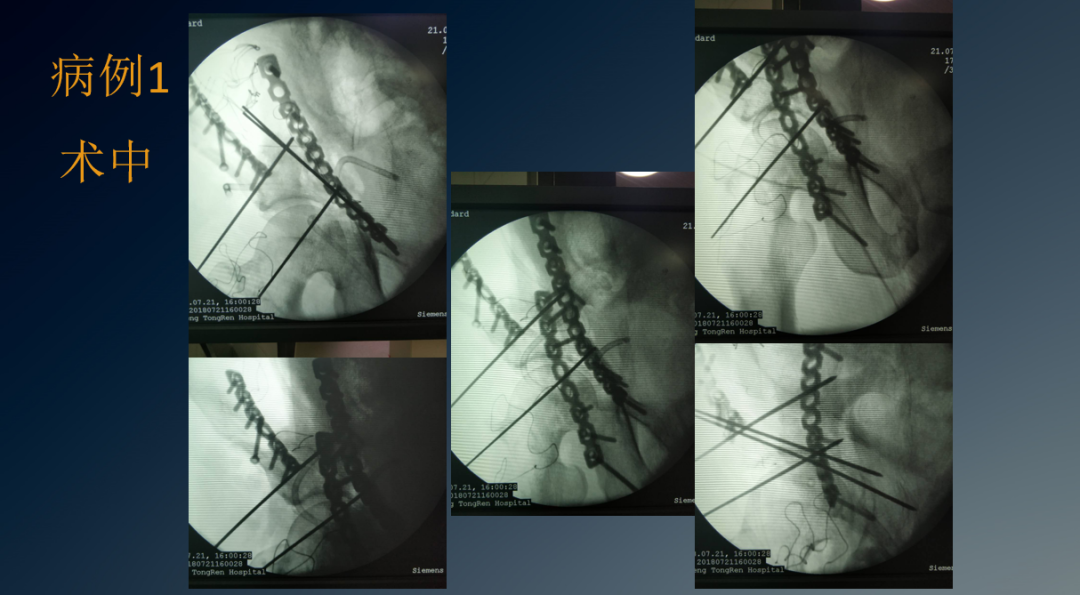

临床病例

适应症:后壁型、后柱型、横断型、后柱加后壁型、横断加后壁型髋臼骨折及伴有难复性或不稳定性脱位、关节内有游离骨折块的髋臼骨折切开复位内固定。需注意的重要解剖结构有坐骨神经、旋股内侧动脉、臀上动脉、臀上神经和臀下神经。

手术入路:取侧卧位或俯卧位,自髂后上棘下方约4厘米处向大转子顶点切一约10 cm唱的弧形切口,切开臀筋膜及阔筋膜,沿臀大肌走行方向钝性分离,在大转子处显露并切断外旋肌和梨状肌,将坐骨神经牵向内侧并小心保护,切断臀小肌及部分臀中肌以显露髋臼后壁及关节囊,清除淤血及纤维性骨痂。